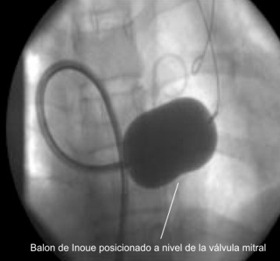

La Valvuloplastia, es un procedimiento de Terapia Endovascular que tienen como propósito aliviar una estenosis valvular, en este procedimiento se usan balones especialmente diseñados para este fin (Inoue).

Actualmente, la Valvuloplastia percutánea con balones es el tratamiento de elección en pacientes con estenosis valvular sintomáticos y en ausencia de contraindicaciones, pero lo más frecuente es que se realice sobre la válvula mitral.

La Valvuloplastía percutánea con balón en la Estenosis mitral, salvo contraindicaciones, es un procedimiento efectivo, que además evita los costos y los riesgos de una cirugía mayor.